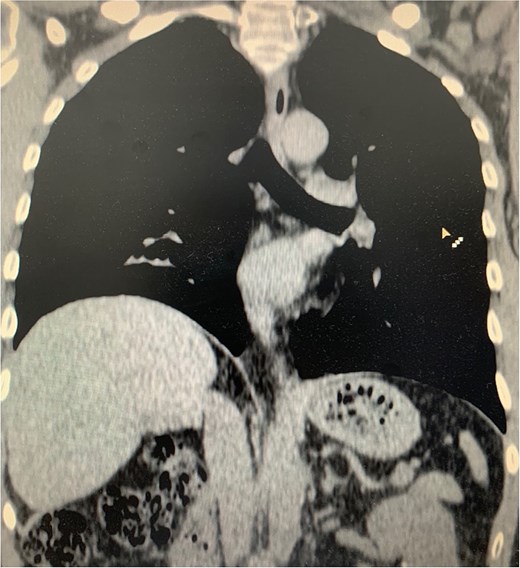

On physical examination, vital signs were stable, and there were no abnormalities. Blood tests and abdominal ultrasound were normal. Gastroscopy shows no lesions. Chest X-ray shows an elevated right hemidiaphragm (Fig. 1). Computed tomography (CT) scan revealed a discontinuity of the right diaphragmatic muscle near the chest wall, with an ~9 × 5 cm hernia defect. This defect established communication between the peritoneal fat and the right pleural space at the lung base (Fig. 2a and b).

(a) Axial CT scan showing an arrow pointing to a discontinuity of the right diaphragm muscle near the right chest wall. (b) Transverse CT scan showing an arrow pointing to a communication between the peritoneal fat of the abdominal cavity and the right pleural space at the lung base.